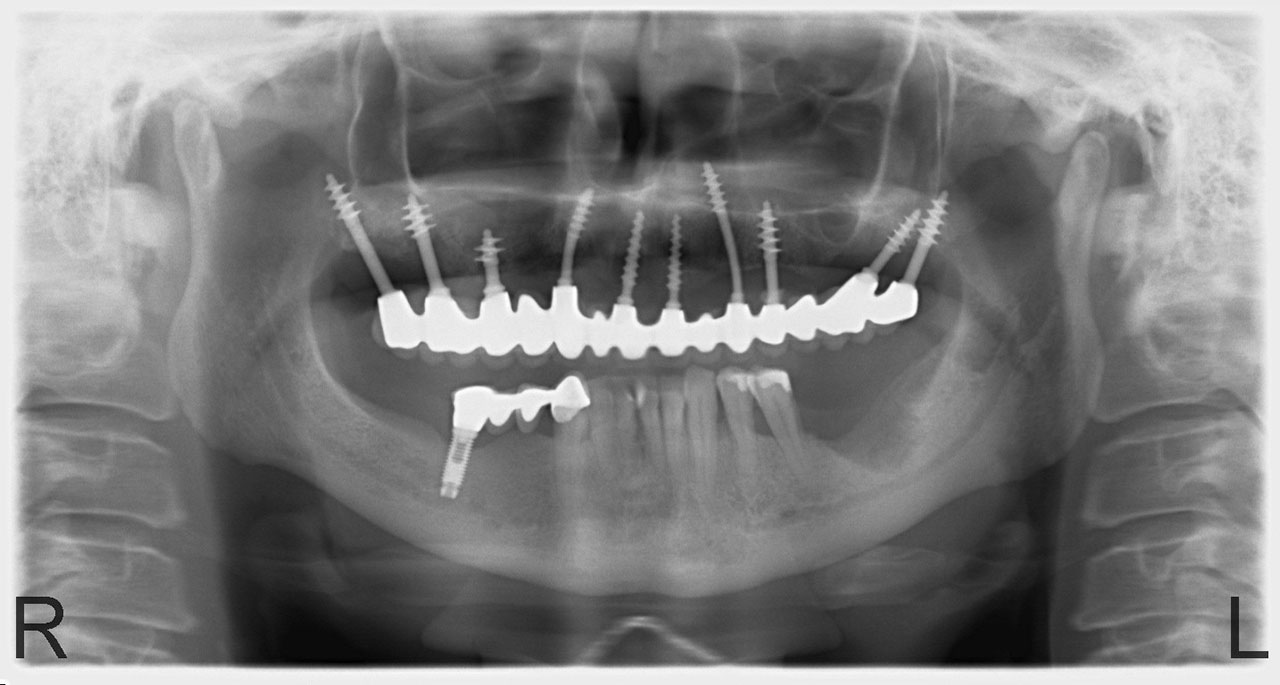

• esettanulmany-14

Alsó- felső fogatlan állcsont teljes implantációs helyreállítása.